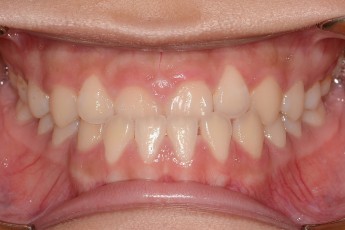

Before

After